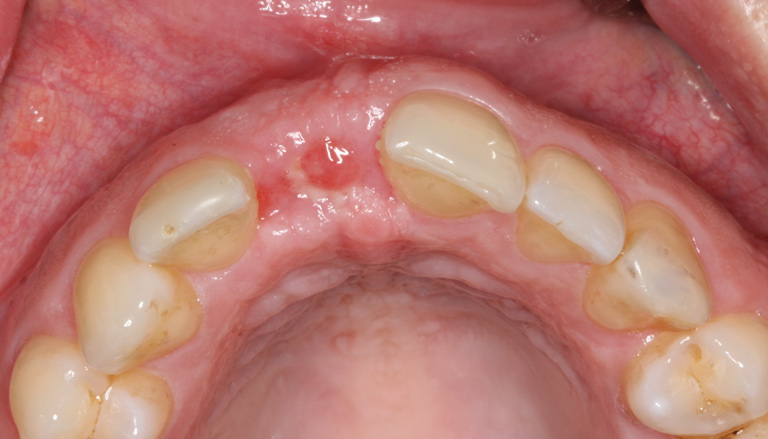

The patient was scheduled for weekly postoperative assessments. The barrier was removed after 5 weeks using a college plier without anesthetizing the patient. After the barrier was removed, osteoid tissue (red connective tissue) was seen covering the bone graft, as anticipated (Figure 9). If bone graft particles are present at the extraction site, they can be left in place, as connective tissue will cover them within 1 to 2 weeks. The epithelium creeps across the reddish connective tissue, and the site becomes pinkish in approximately 2 weeks, as occurred in this case (Figure 10).6

Fig 9. Wound healing was evident immediately after d-PTFE barrier removal. Red osteoid tissue was present.

Figure 9

Fig 10. At 7 weeks follow-up, keratinized tissue was present.

Figure 10